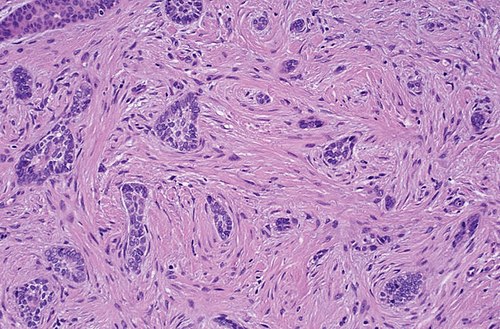

📷 תמונה קלינית

אקנה ציסטית קשה

אקנה וולגריס קשה - ציסטית: נצפים נודולים וציסטות דלקתיות מרובים על הפנים, לצד פפולות ופוסטולות. שימו לב להצטלקות ולנגעים הדלקתיים העמוקים המאפיינים אקנה בדרגה קשה, המהווים אינדיקציה לטיפול סיסטמי באיזוטרטינואין.

Credit: James Heilman, MD | CC BY-SA 3.0 | Wikimedia Commons